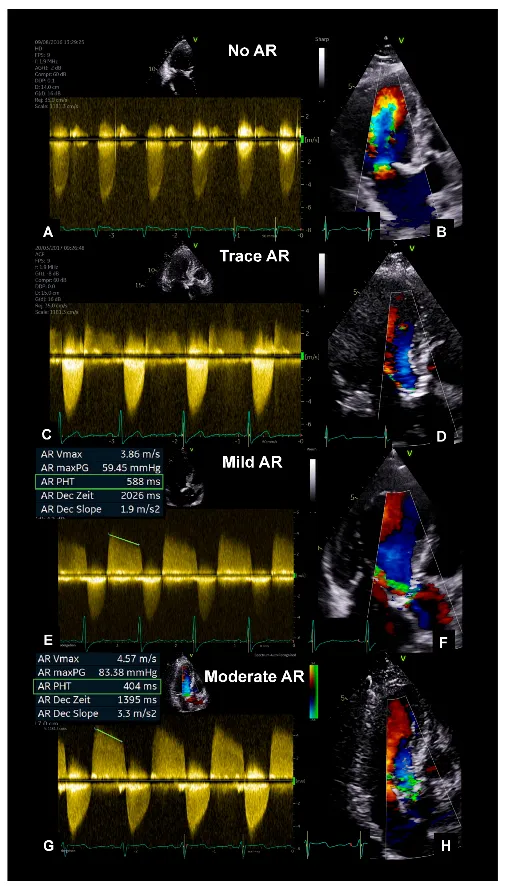

Aortic Regurgitation - The Leaky Gate

- Etiology: Aortic root dilation (Marfan syndrome, syphilis), infective endocarditis, rheumatic fever.

- Pathophysiology: Backward flow into LV → LV volume overload → eccentric hypertrophy → ↑ stroke volume but eventual systolic dysfunction.

- Symptoms & Signs: Palpitations, dyspnea. ↑ Systolic & ↓ diastolic pressure → wide pulse pressure.

- Eponyms: Water-hammer pulse (Corrigan's), de Musset's sign (head bobbing), Quincke's pulses (capillary pulsations).

- Murmur: High-pitched, blowing, early diastolic decrescendo murmur best heard at the left sternal border.

⭐ Exam Favorite: An Austin Flint murmur, a mid-diastolic rumble, can be heard. It's caused by the regurgitant jet striking the anterior mitral valve leaflet, mimicking mitral stenosis.